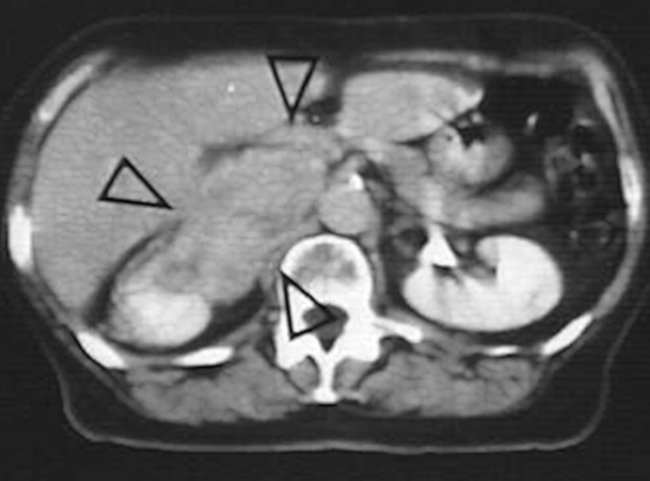

Односторонний характер патологического процесса наблюдается у людей старше 40 лет. При выполнении КТ и МРТ можно обнаружить то, что опухоль имеет четкие границы, как только она начинает ускоренно расти, можно заподозрить ее переход в более агрессивную форму.

Опухоли надпочечников диагностировать достаточно сложно. Появление современных информативных способов обследования позволяет обнаружить рак на ранней стадии его развития.

УЗИ — наиболее простая и эффективная диагностическая процедура, позволяющая определить локализацию и размеры новообразования.

Кроме того, этот метод используется и для выявления вторичных очагов в близлежащих и отдаленных лимфатических узлах и органах. При наличии лишнего веса этот способ может оказаться недостаточно эффективным.

Анализ крови на гормоны отражает повышение уровня кортизола, ренина и хромогранина. Эти показатели позволяют оценить степень нарушения гормонального баланса организма. МРТ и КТ используются для обнаружения вторичных очагов

Дополнительно назначается суточный мониторинг колебания уровня кортизола и анализ на метанефрины. Эти процедуры позволяют обнаружить рак надпочечников на любой стадии его развития.